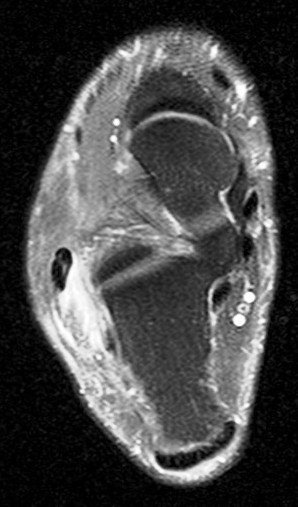

Figure 1 for case peroneal dislocation

Figure 1

Both peroneals are dislocated around fibula. Retinaculum is torn. Initial case was missed. Patient walking around for nearly a year like this.

peroneal dislocation